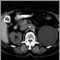

Kidney cyst with gallstones, CT scan